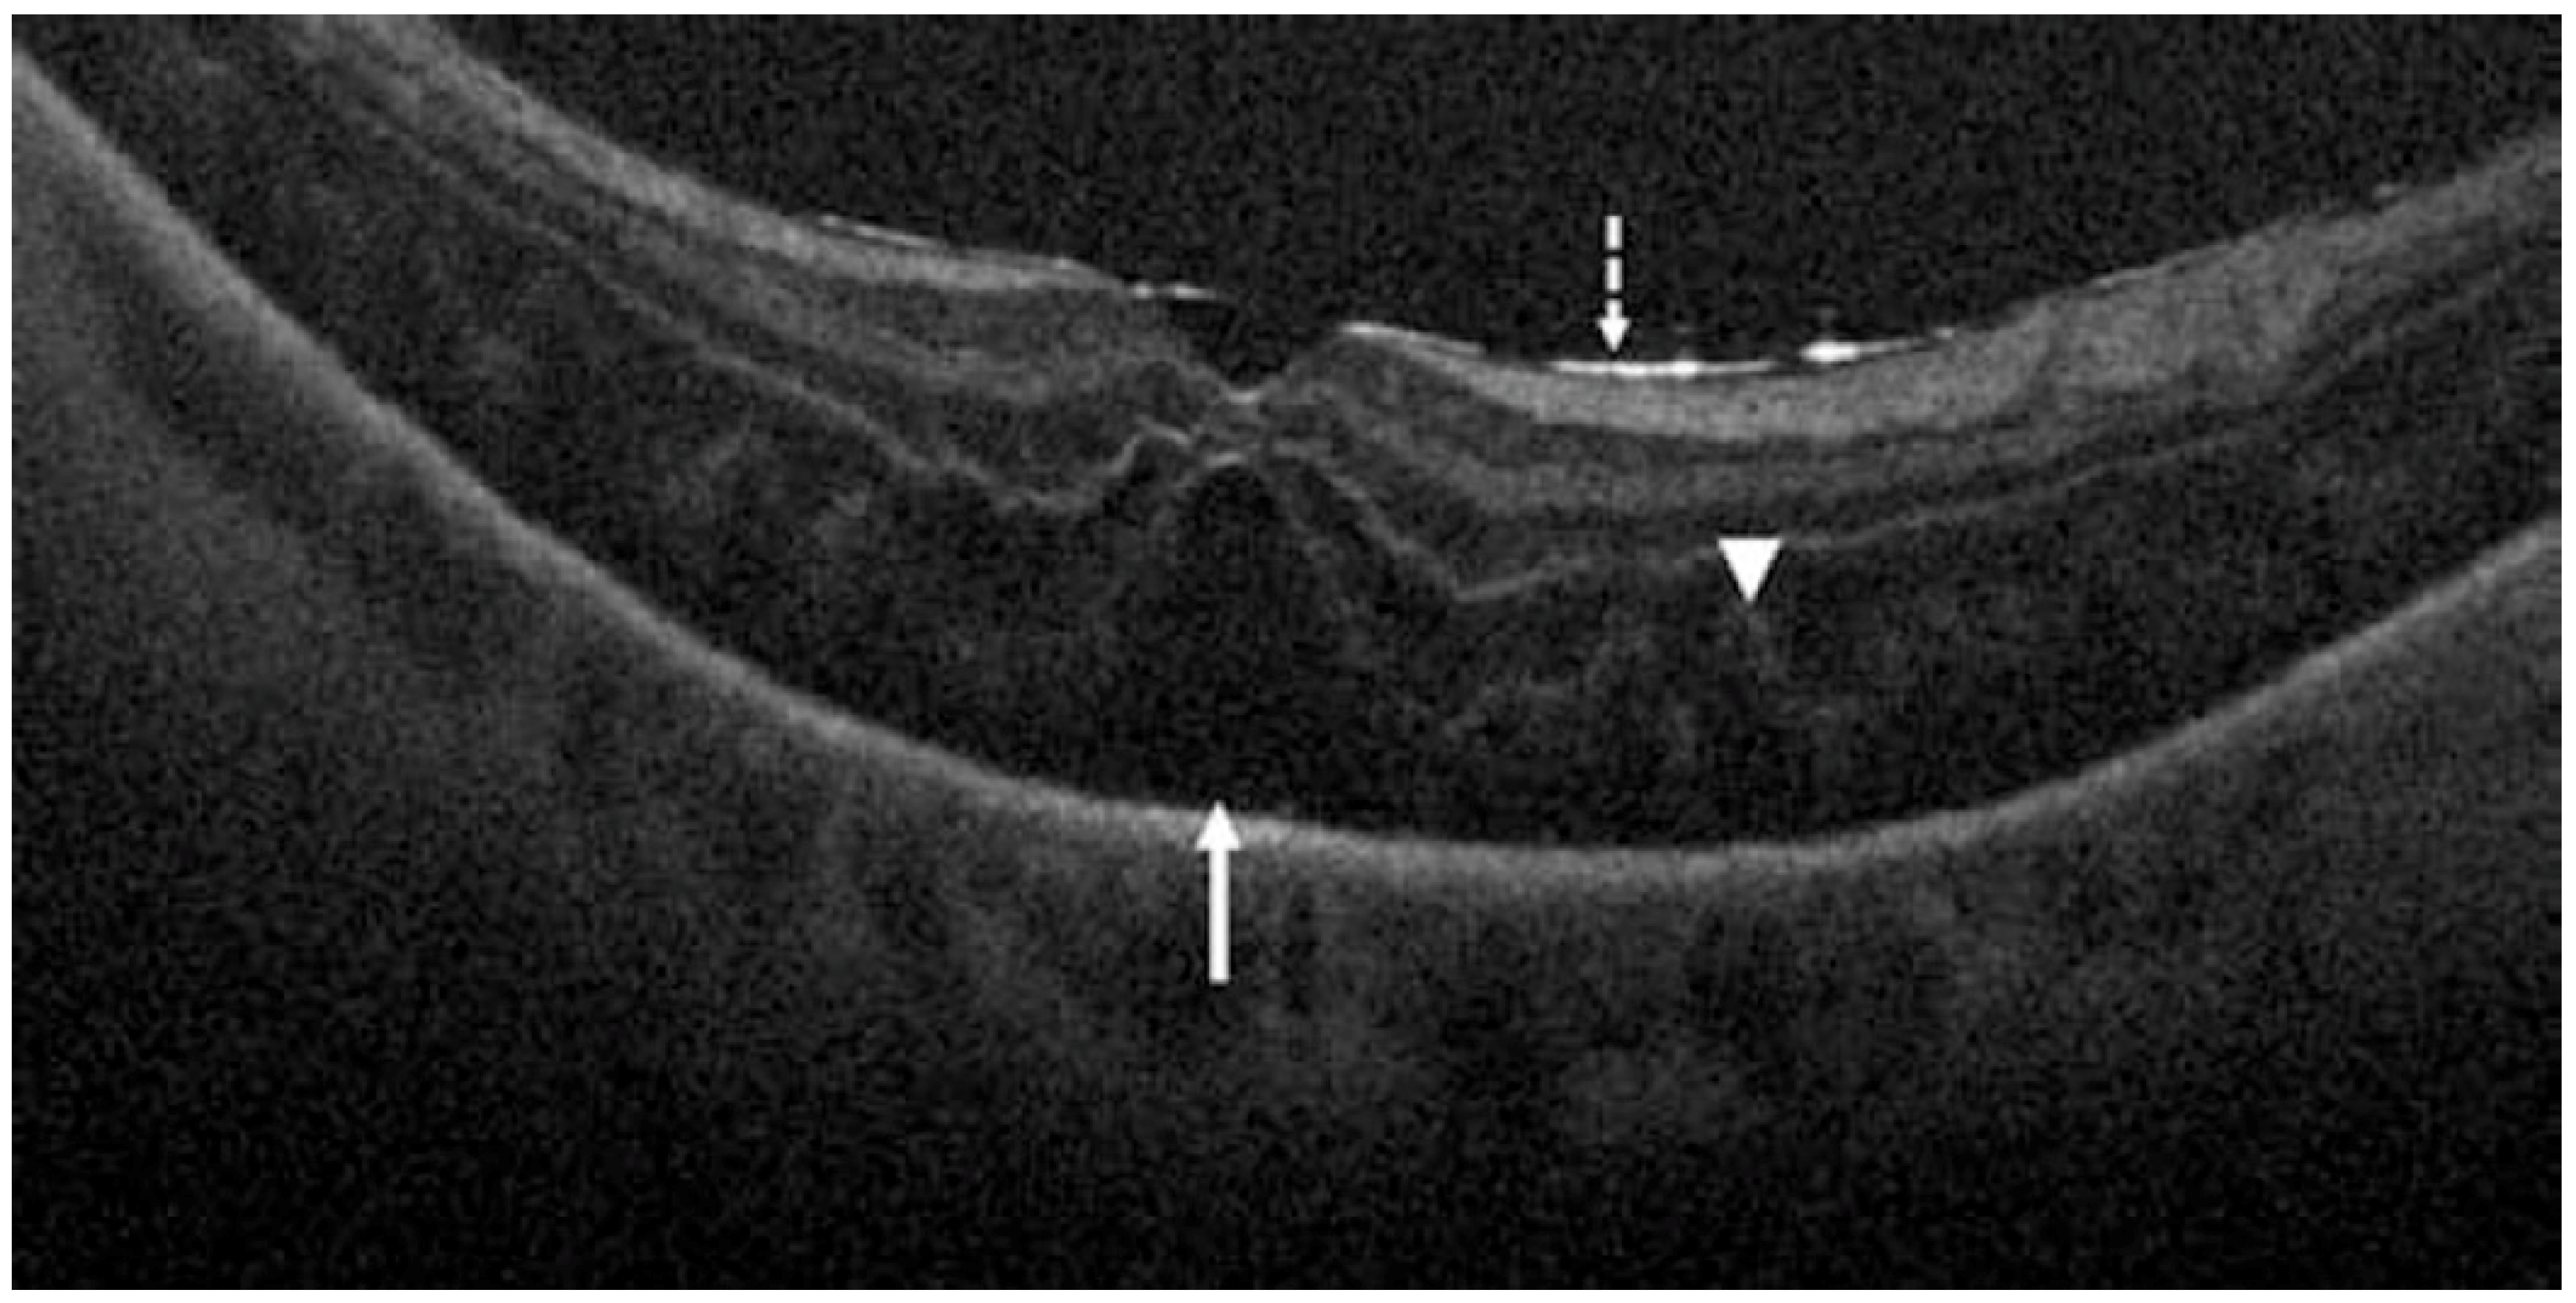

- Takahashi, H.; Tanaka, N.; Shinohara, K.; Yokoi, T.; Yoshida, T.; Uramoto, K.; Ohno-Matsui, K. Ultra-Widefield Optical Coherence Tomographic Imaging of Posterior Vitreous in Eyes With High Myopia. Am. J. Ophthalmol. 2019, 206, 102–112. [Google Scholar] [CrossRef]

- Schranz, M.; Roberts, P.K.; Motschi, A.R.; Hollaus, M.; Mylonas, G.; Sacu, S.; Pircher, M.; Hitzenberger, C.K.; Schmidt-Erfurth, U. Tracking of fibrosis growth in neovascular age related macular degeneration. Investig. Ophthalmol. Vis. Sci. 2022, 63, 1025–F0272. [Google Scholar]